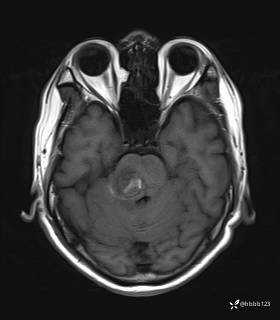

患者男,51岁。

简要病史:患者自述于1周前至某人民医院发现脑干肿瘤(具体不详),为求进一步诊断至我院就诊。

完善颅脑MRI平扫+增强,颅脑CT平扫:

T2: